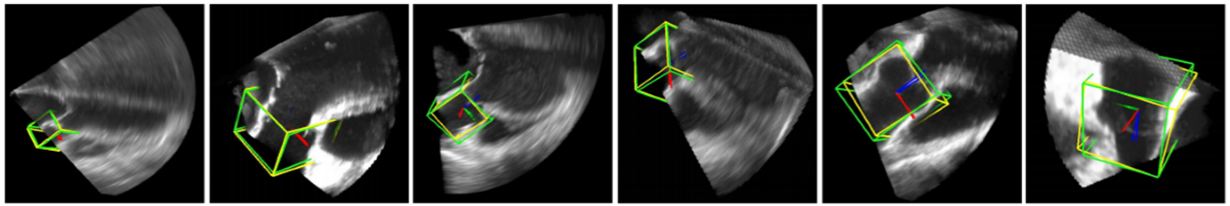

where represents the 3D translation, denotes the 3D orientation and signifies the 3D scale space. The DC applied in this paper is Fully Connected Network. As observed in Eq. 14, a rough estimate is made on the position, orientation and scale of LV by using three DCs. The first DC is used to estimate the position of LV using 3D translation. By using the position estimate of the first DC, the second DC is used to estimate the position and orientation of LV. At last, by taking into account the position and orientation estimate from the second DC, the third DC estimates the position, orientation and scale of the LV. In the border estimation stage, DL-based active shape model is applied to guide the shape deformation. In order to increase computational efficiency and prevent overfitting, sparsity is introduced into the network by gradually dropping neural connections without affecting network performance. The dataset is taken from 869 patients containing 2,891 3D volumes from different vendors. The results have shown considerable improvement over state of the art Marginal Space Learning (MSL). The MSDL position error is computed at 1.47 mm which is far lower compared to 3.12 mm in MSL. The MSDL corner error is found to be 2.80 mm which is almost half the corner error of 5.42 mm in MSL. The corresponding model is given in Figure 12.

Figure 13Deep Classifier-based 3D LV segmentation model outputs. The auto detected bounding box is shown in green while the GT bounding box is shown in yellow (reproduced with permission from (43)).

The resultant images are shown in Figure 13. The results provided in this study are not sufficient to judge the efficiency of the scheme. However, this method is the first application of DL in 3D imaging and therefore can be considered a benchmark in volumetric image parsing.